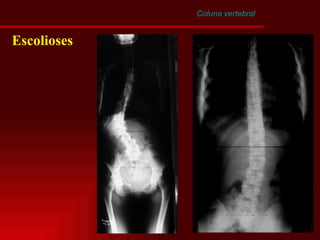

Coluna vertebral Escoliose

Coluna vertebral Escolioses Definição –  é uma curvatura lateral da coluna vertebral no plano coronal Etiologia Congêntita – Marfan, diastematomielia Idiopática Neuromuscular - poliomielite Outras – fraturas e infeccões

Coluna vertebral Escolioses

Coluna vertebral Método de Lippman - Cobb